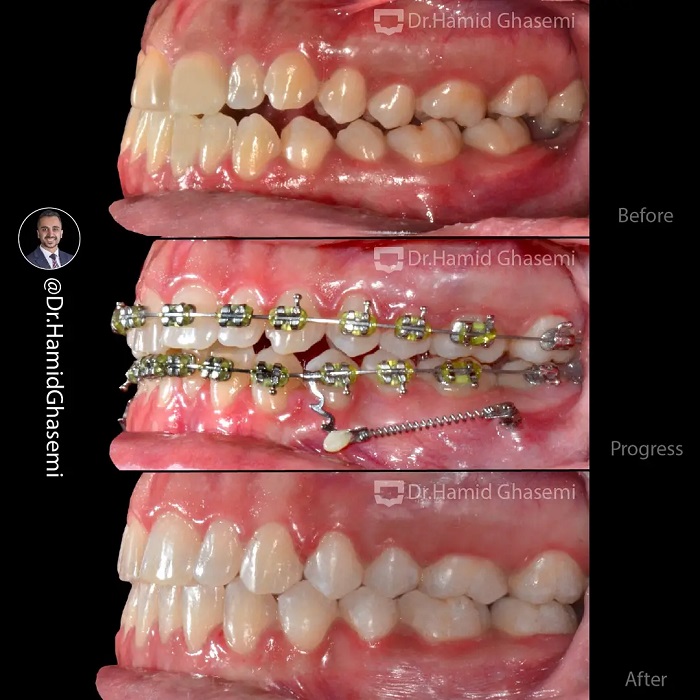

شماره پرونده : M.98_1549

درمان ارتودنسی بدون جراحی فک در کیس کلاس ۳ با بیرون زدگی فک پایین با استفاده از دیستالیزیشن فک پایین بعد از کشیدن دندانهای عقل فک پایین به کمک تکنیک Tads system ( اسکرو در باکال شلف فک پایین + فنرهای fatigue resistante ) در مدت ۲۰ ماه انجام شد. این کیس بوردر لاین نمونهای بارز از اهمیت انتخاب روش درمان ارتودنسی با و یا بدون جراحی فک را نشان میدهد که تا چه میزان امکان درمان ارتودنسی بدون جراحی فک با استفاده از تکنیک Tads system وجود دارد.

Non surgical orthodontic treatment of class 3 case with prognathic mandible done by distalizing lower dentition after extration of lower 3rd molars using Tads system (screws in buccal shelf + fatigue resistant closed coil spring) within 20 months. This case is an example of borderline case which the decision for surgical or non surgical treatment plan should be carefully planned to avoid surgery when ever it is possible with the aid of Tads system.